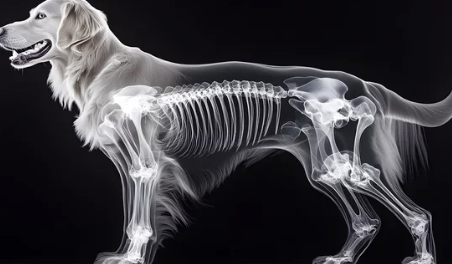

강아지 관절염은 관절에 염증이 생겨 통증과 움직임 제한을 유발하는 질환입니다. 특히 나이가 들수록 발병 가능성이 높아지며, 소형견보다는 대형견에게 더 흔히 발생합니다.

관절염은 진행성 질환이기 때문에 방치할 경우 강아지의 움직임뿐 아니라 전반적인 건강에도 영향을 미칠 수 있습니다.